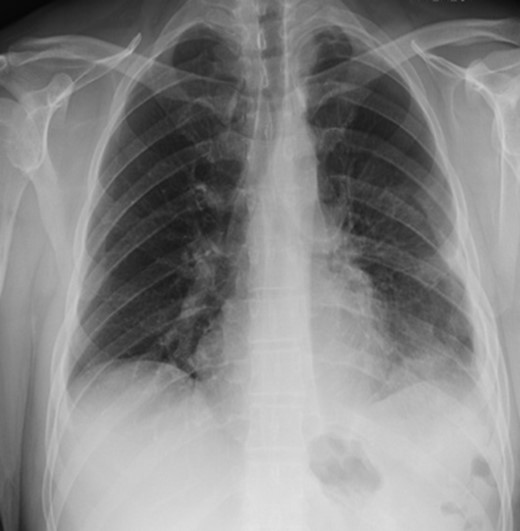

Two days later, the patient re-presented to the emergency department with left-sided pleuritic chest pain. The heart rate was 92 beats/min and the respiratory rate was 23 breaths/min on room air. The patient was stable, looked well, and his pain resolved almost entirely at time of examination. Clinically relevant labs showed a WBC of 8 × 109/L (normal range: 4–11 × 109/L). The CT did not show any significant enlargement of pneumoperitoneum; however, significant rightward shift of the mediastinum was noted. So we suggested worsening tension in the left hemithorax with further collapse of the left lung (Fig. 3). Despite being clinically stable, the mediastinal shift which was not present on the previous admission was concerning and thus the patient was taken to the operating room with the decision to repair the hernia. A left thoracotomy was used to enter the chest cavity. There was severe atelectasis of upper and lower lobes. We immediately noted a large hernia sac which encompassed the entire chest cavity and the remaining diaphragmatic muscle was significantly thinned out. The hernia sac was opened in order to identify the source of the pneumoperitoneum seen on imaging which we had suspected to be of gastric origin. Upon examination of the abdominal contents which required meticulous dissection off the herniated diaphragm from chronic adhesions, we were able to identify a well-developed perforated gastric ulcer on the anterior surface of the greater curvature of the stomach (Fig. 4). This ulcer was resected with a wedge GIA stapler and the hernia was subsequently closed by bringing the muscles together and imbricating the closure with the redundant sac using prolene sutures. Upon closure, we did not place a mesh due to the possible contamination from the gastric perforation. When the repair was complete and the patient taken off the one-lung ventilation, his lungs immediately pinked up and re-expanded. Overall, the patient tolerated the procedure very well without any post-operative complication. Two days later, we carried out an upper GI series which showed no evidence of any extravasation and his diet was advanced. On the sixth post-operative day, the patient was discharged home. He was re-evaluated in clinic 2 weeks later and continued to progress well with a stable repeat chest x-ray (Fig. 5).

Chest x-ray on follow-up visit post-operative showing stability of repair.